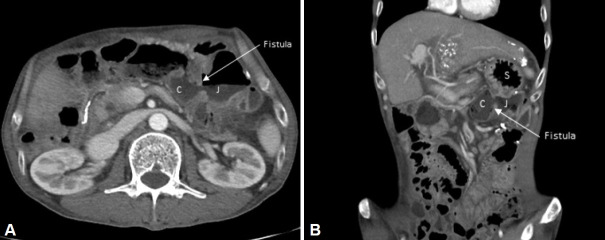

胃空肠结肠瘘是胃空肠吻合术中一种罕见但严重的并发症,通常是由于胃手术中迷走神经切除不充分或不完全造成的。最常见的症状包括呕吐、慢性腹泻和体重减轻,手术修复是这种情况的最终治疗方法。男,51岁,因上腹部疼痛及慢性腹泻就诊。20年前在另一家医院因胃癌做过胃手术。上消化道内窥镜及腹部电脑断层扫描证实诊断为胃空肠结肠瘘。在这个病例报告中,我们介绍了胃空肠结肠瘘的临床特征和诊断方法。

Gastrojejunocolic fistula, a rare but serious complication of gastrojejunostomy often results from inadequate resection or incomplete vagotomy during gastric surgery. The most common symptoms include feculent vomiting, chronic diarrhea, and weight loss, and surgical repair is the definitive treatment for this condition. A 51-year-old man presented to our hospital with upper abdominal pain and chronic diarrhea. He had a history of gastric surgery for gastric cancer, 20 years prior at another hospital. Upper endoscopy and abdominal computed tomography confirmed diagnosis of a gastrojejunocolic fistula. In this case report, we present the clinical features and diagnostic approaches for gastrojejunocolic fistulas.